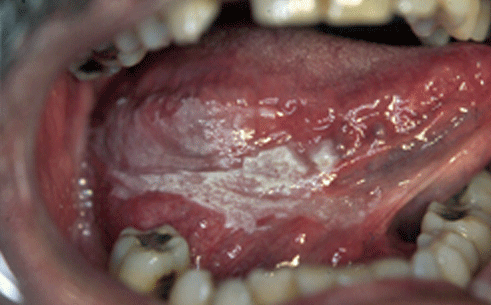

Estas patologías se pueden manifestar como lesiones blancas, lesiones rojas, ulceraciones o, tumoraciones.